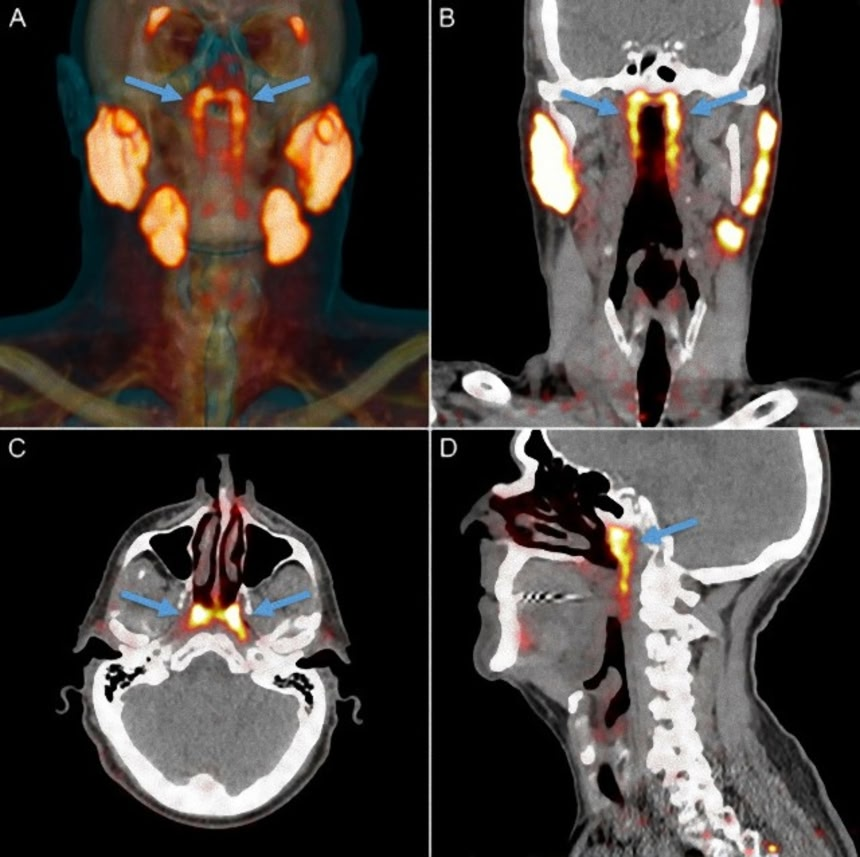

その「未知の臓器」は、オランダがん研究所のグループが「前立腺特異的膜抗原(PSMA) PET-CT」という最新の検査機器で前立腺がんの患者を検査していたときに偶然見つかった。

PSMA PET-CTは放射性グルコースを注入することで、これまでは見つけられなかった腫瘍を検出することができる。ところが、その検査では鼻咽頭の後ろに誰も気がつかなかった1対の器官が浮かび上がったのだ。

鼻の後ろ、口蓋の上のあたりで見つかった唾液腺は、PSMA PET-CT検査を受けた100人全員で検出されており、2体(男女)の検体の解剖によっても、縦長の器官と鼻咽頭壁へむけて開いた管が確認された。

また腺組織が含まれていることも確認されており、どうやら4つ目の主要な唾液腺であると考えられるようだ。研究の発表時点では、耳管隆起という軟骨の上にあることから「耳管腺(tubarial glands)」という名称が提案されている。